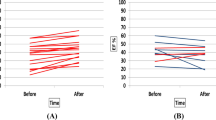

T1/T2 mapping

One cyclist was excluded because of non-diagnostic T1/T2 mapping image quality due to ECG-gating problems. Myocardial T1 relaxation times increased significantly post-exercise (1133 ± 48 to 1182 ± 46 ms, p < 0.001) in the 17 finishers (Fig. 3a and supplemental Fig. 2), while no significant change in T2 mapping (43.9 ± 2.8 to 44.1 ± 2.5 ms, p = 0.474) (Fig. 3b) was observed at SA maps (Table 3). Interobserver reproducibility (ICC, single measures) of blinded native T1 and T2 mapping measurements was excellent: T1: 0.985, 95% confidence interval (CI) 0.972 to 0.992; T2: 0.956, 95% CI 0.919–0.976. Bland–Altman plots with 95% limits of agreement confirmed the close agreement of both observers (supplemental Fig. 3a, b).

A third CMR 18-20 h post-exercise, performed in a randomly selected subgroup of 8 riders, revealed a significant decrease of T1 relaxation times compared to 3–6 h post-exercise (1180 ± 56 ms versus 1130 ± 67 ms, p = 0.025) and similar values compared to the rest CMR (1117 ± 50 ms versus 1130 ± 67 ms, p = 0.483). T2 relaxation times did not change significantly at 3–6 h (44.8 ± 3.6 ms versus 44.6 ± 3.5 ms, p = 0.538) and at 18–20 h (44.8 ± 3.6 ms versus 45.6 ± 4.1 ms, p = 0.4) post-exercise compared to rest CMR (all p-values > 0.05) in this subgroup.

Post-race cTnI release was strongly correlated with T1 myocardial relaxation time increase (r = 0.702, p = 0.002) (Fig. 4a). A higher HR difference (post-exercise versus rest CMR) was not related to higher post-exercise T1 myocardial relaxation time (r = − 0.235, p > 0.05) and troponin modifications (r = − 0.385, p > 0.05).cTnI release was also correlated with post-race RV dysfunction (r = 0.562; p = 0.025) in our cyclists (Fig. 4b).

Correlation between exercise-induced Troponin I release and increased post-race T1 myocardial relaxation time (a), and right ventricular dysfunction (b). Increased post-race T1 myocardial relaxation times (ms) and Troponin I release (ng/L) were strongly correlated (r = 0.703; p = 0.002) (a); more pronounced post-race right ventricular dysfunction was correlated with higher troponin release (p = 0.025; r = − 0.562) in our cyclists (b). Spearman’s rank correlations were used to test correlations between post-race Troponin I changes (Δ LnTroponin I), and post-exercise T1 mapping (Δ T1 mapping) and right ventricular EF (Δ right ventricular ejection fraction) modifications. ms milliseconds, EF ejection fraction, Ln natural logarithm